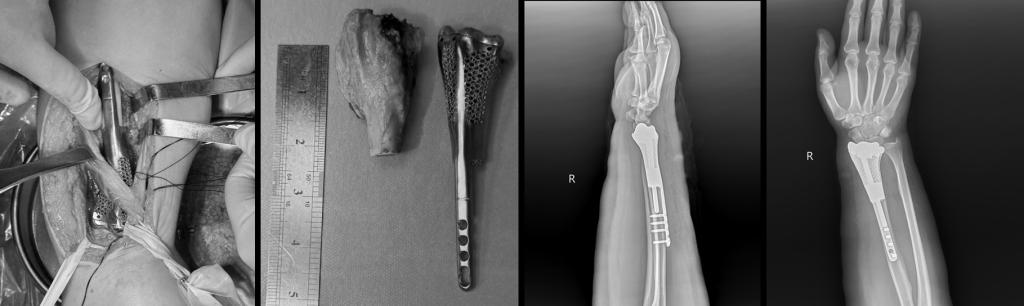

经过严密、反复的计算机模拟手术,与患者完全适配的3D打印多孔桡骨假体成功设计并打印。最终,手术由王栋教授主刀,在赵波副教授、欧阳鹏荣主治医师和李宇欢住院总医师的紧密配合下,在麻醉科镇路明教授及李塞鹏、彭维护士全程保驾护航下,仅1个半小时就成功完成了肿瘤切除、假体置换、肌腱缝合重建手术,手术保护了重要的神经、血管,既完整彻底切除桡骨肿瘤,同时也最大限度地保留正常的组织和结构。手术过程顺利,术后患者康复良好,患者术后肢体功能没有任何丧失,病理检查提示切缘无肿瘤细胞残留,患者痊愈出院。